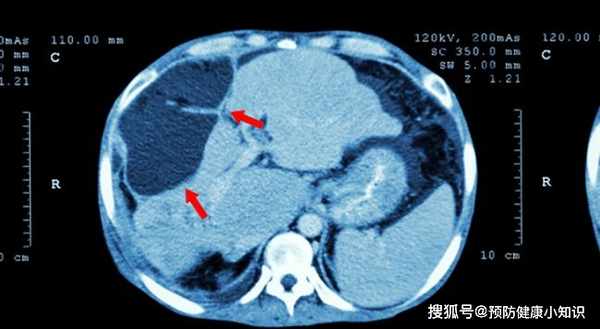

然而,一天正在上班,發現右手使不上力,右肩疼痛從陣痛變為持續性疼痛了,馬上請假,去醫院檢查,經醫生建議,去內科做一下肝功檢測,才發現轉氨酶高達320,肝髒表面出現結節,確診中期肝硬化,這讓劉女士大吃一驚。

肝區疼痛是肝病患者非常常見的病症之一。

主要是,由於肝細胞被病菌侵蝕後,體積越來越大,壓迫到肝臟周圍包裹的肝包膜,肝包膜內含豐富的神經末梢,因而會感到肝區疼痛。